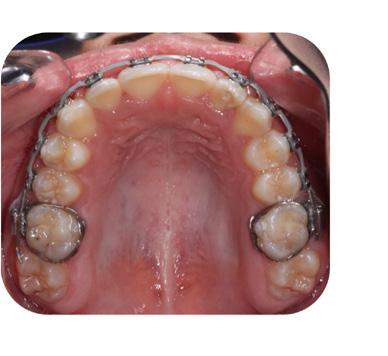

FIG. 13D: Post-treatment, maxilla, occlusal view

FIG. 13E: Post-treatment, mandible, occlusal view